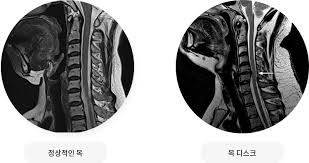

목디스크, 즉 경추디스크는 경추(목의 부분) 영역에서 발생하는 디스크 손상을 의미합니다. 이러한 디스크는 각 척추 사이에 위치하며, 척추의 충격을 흡수하고 유연성을 제공하는 중요한 역할을 합니다.

목디스크는 주로 디스크의 견봉이 손상되거나 내부의 젤이 누출됨으로써 발생합니다. 이런 손상은 디스크의 터짐, 미세한 틈새, 혹은 디스크에 가해지는 과도한 압력 때문에 발생할 수 있습니다

목디스크는 하중이 한 부위에 집중되어 경추 사이에 있는 추간판이 파열되고 내부의 수핵이 변위될 수 있는 상태를 가리킵니다.

이러한 상태는 공식적으로는 경추 추간판 탈출증으로 알려져 있으며, 목의 추간판이 손상되어 통증과 불편을 초래할 수 있습니다. 목디스크는 일상 활동에서의 부적절한 자세나 무리한 운동, 또는 직업적 요인으로 발생할 수 있습니다.